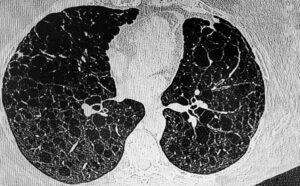

Low-dose CT lung cancer screening is a quick, painless imaging test that uses minimal radiation to create detailed pictures of your lungs, helping detect lung cancer at its earliest and most treatable stages.

During your low-dose CT lung cancer screening, you’ll lie comfortably on your back while a specialized scanner captures detailed images of your lungs in less than 60 seconds.

Low-dose CT is highly effective at detecting early-stage lung cancer and is far more sensitive than chest X-rays.

• Detects nodules as small as 2–3 mm

• Finds lung cancer when it is small and before it spreads

• Much more sensitive than chest X-rays